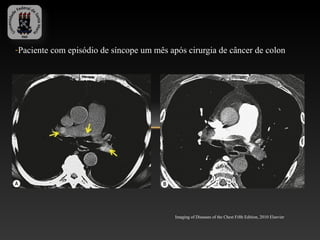

-Paciente com episódio de síncope um mês após cirurgia de câncer de colon

Imaging of Diseases of the Chest Fifth Edition, 2010 Elsevier